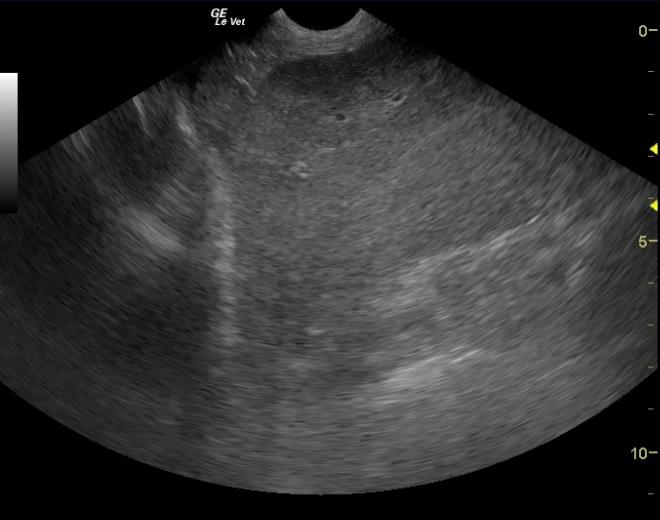

A 9-year-old MN English Pointer was presented for decreased appetite, weight loss, lethargy, and halitosis. Physical examination findings were generalized muscle wasting and slightly pale mucous membranes. The only abnormality on urinalysis was trace proteinuria; UPC showed borderline proteinuria. Abnormalities on CBC were anemia and thrombocytopenia. The patient was treated with Prednisone pending an ultrasound.